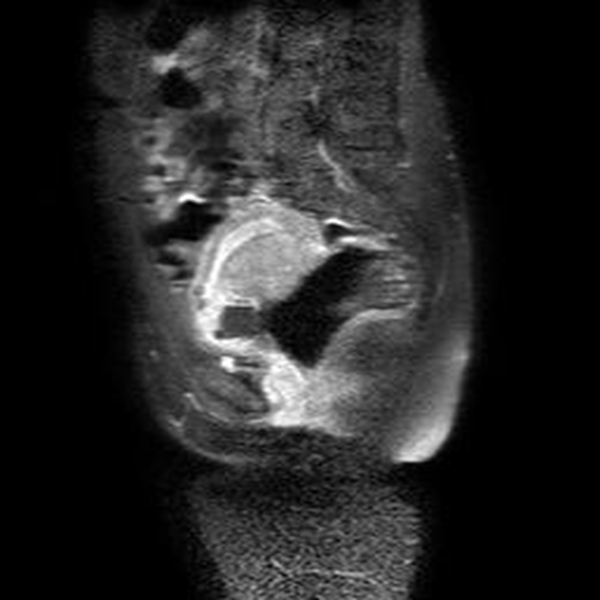

Se realizó una RNM (Philips 1.5 Tesla) que permitió confirmar el diagnóstico de EEC (figuras 5 a 8).

El propósito de la RMN es aportar información adicional para mujeres que necesiten un diagnóstico preciso, caracterización del tejido y ubicación espacial. Algunas indicaciones de la resonancia en el EE son las complicaciones asociadas, hallazgos ecográficos no concluyentes o complicaciones del EE, como las localizaciones abdominal, intersticial, miometrial o cervical (26).

La localización cervical de un EE por debajo del orificio cervical interno puede confundirse con un aborto espontáneo en curso, con enfermedad trofoblástica, con un pólipo endometrial que protruye por el canal cervical o con una placenta de implantación baja (27).

Jung y cols. (28) encontraron como hallazgos en RMN de EEC una masa mal definida con señales muy heterogéneas en T2, hiperintensidades internas e irregulares en T1, con un anillo circunferencial o parcial de baja intensidad de señal, con realce periférico irregular del componente sólido papilar, acompañado de vacíos de señal de morfología tubular. Esto va en concordancia con lo referido por Tamai y cols. (27), que describen típicamente el EEC como una masa hemorrágica, heterogénea y con realce intenso de los componentes papilares del tejido.

Una secuencia útil en la identificación del hematoma reciente es el T2*, que podría remplazar el uso del gadolinio en esta indicación particular. La sensibilidad del 95 % y la especificidad del 100 % de esta secuencia mejora significativamente el desempeño de la resonancia en el diagnóstico de EE (29).

El uso de gadolinio intravenoso incrementa la especificidad en el diagnóstico de embarazo tubárico, lo que permite diferenciar el realce normal de la trompa de un hematoma reciente. En este caso, este principio nos ayudó a delimitar la afectación decidual y a descartar la presencia de un hematoma asociado (30). La resonancia con gadolinio también se ha utilizado en el seguimiento del tratamiento conservador del EEC (31).